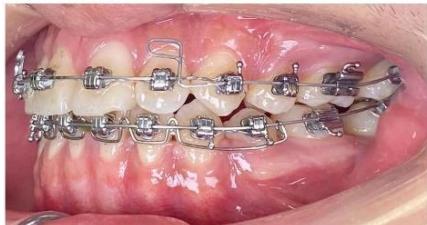

### c) Incisor Retraction using Segmented Mechanics

After completion of canine retraction, the incisor segment was retracted using segmented mechanics according to the Ricketts Bioprogressive philosophy. Retraction arches in both arches were designed to achieve three objectives simultaneously: (i) controlled incisor retraction; (ii) activation of an intrusive component of approximately 2-3 mm to counteract anterior tooth extrusion, which is particularly critical in high-angle patients; and (iii) generation of strong and stable positive torque to achieve three-dimensional control of incisor root movement, especially in the mandibular arch [19-21]. The retraction arches were activated at a rate of approximately 1.5 mm per month while maintaining torque and vertical control.

During the finishing phase, the ART torque spring was continuously maintained in the mandibular incisor region to reduce secondary negative torque and to assist in directing the incisor roots into cancellous bone, thereby protecting the labial cortical plate during the stage when retraction forces generate the most unfavorable moments [22-24].

After the occlusal objectives were achieved, the patient was progressed through finishing archwires (0.016 NiTi; 0.016×0.022 NiTi; 0.017×0.025 NiTi; and 0.017×0.025 stainless steel), in combination with intermaxillary elastics (3/16-inch, 3.5 oz) for midline correction and occlusal settling. Subsequently, space reopening was observed between the maxillary lateral incisors (tooth 2) and canines (tooth 3) bilaterally. A space-closing archwire with L-shaped loops positioned between teeth 2 and 3 was fabricated, and space closure was activated at approximately 1.5 mm per month over a two-month period, resulting in complete space closure. Thereafter, both arches were placed on 0.017×0.025 stainless steel archwires with full-arch elastomeric chains. Intermaxillary elastics were continued to assist in midline correction and to achieve optimal intercuspation.

Figure 9: Re-leveling and alignment phase following anterior space closure of the four incisors